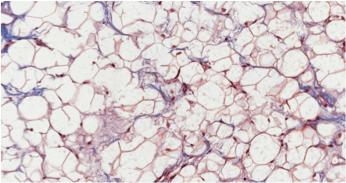

Tissu adipeux blanc:

- TABlanc.png (156.41 Kio) Vu 263 fois

Ici c'est l'image tombé il y a 2 semaines il me semble

Donc là on remarque que les noyaux ne sont plus centraux et bien en périphérie avec une forme plutôt ovale plaqué contre la membrane plasmique du fait de l'unique enclave lipidique hypertrophié